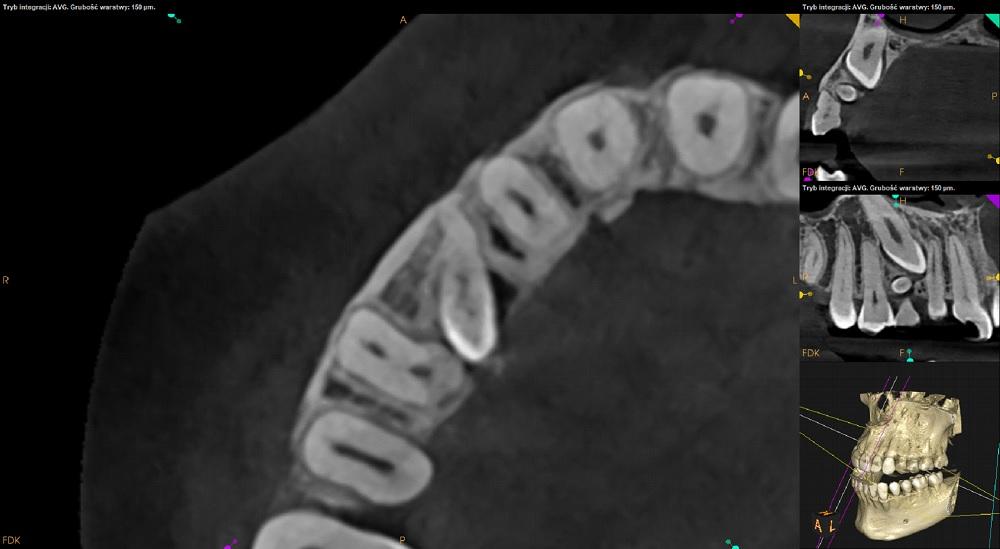

Tomografia szczęka i żuchwa.

Ząb 13 – zatrzymany. Położony pionowo skośnie, koroną skierowany w stronę mezjalną i podniebienną. Zrotowany w stronę dystalną.

Korona zęba 13 przylega do korzenia zeba 12 – resorpcja korzenia niewidoczna. Wierzchołek korzenia zęba 13 zagięty.